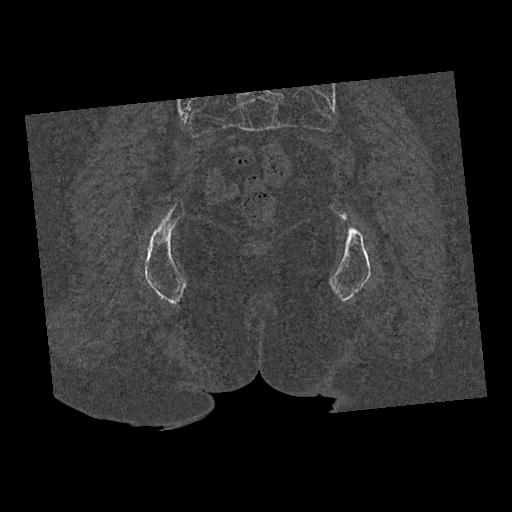

100703 1/27 両股正面+軸 1/29 両股正面+軸 94歳女性 パンソンロン

46666 1/28 両股正面+軸と 1/26 右手関節 2R 76歳女性 右転子部骨折

37 1/18 両股正面+軸 1/22 2R 86歳女性 右転子下

91569 3/25 両股正面とラウエン 70歳女性 人工骨頭+バンクーバー